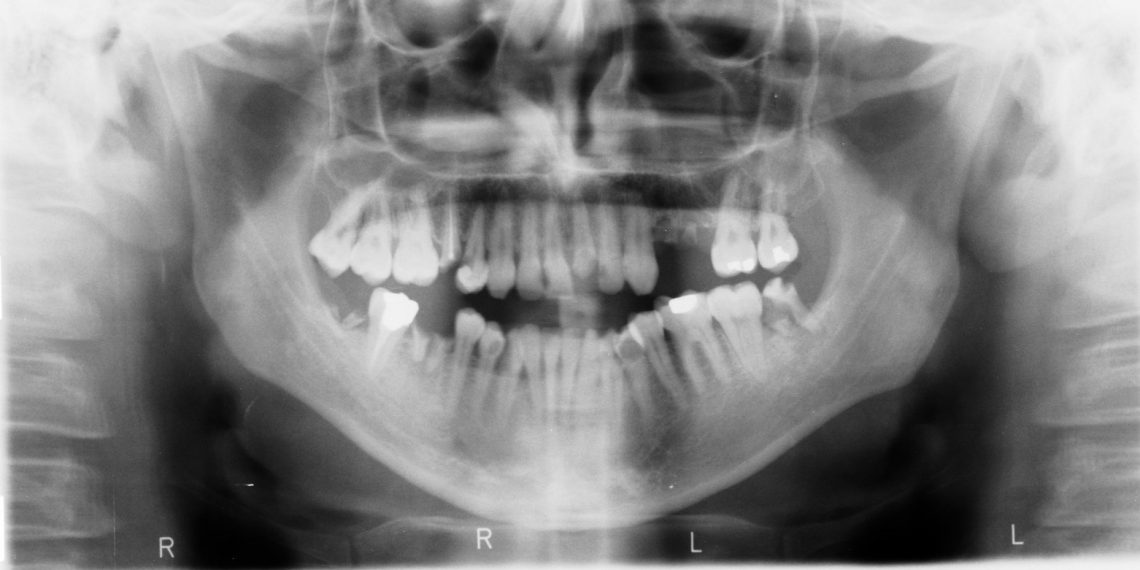

Po co wykonuje się tomografię stomatologiczną?

Aby w szczegółowy sposób zobaczyć i zobrazować uzębienie jak i konkretną okolicę zęba warto wykonać badanie diagnostyczne jakim jest tomografia.

Tomografia zębów jest bezpieczna metodą diagnostyczną. Dzięki niej można bardzo dokładnie ocenić stan uzębienia. Jest to bardzo szybka metoda. Już od razu po wykonaniu lekarz otrzymuje rzeczywisty oraz trójwymiarowy obraz tkanek miękkich, zębów jak również zatok szczękowych.…